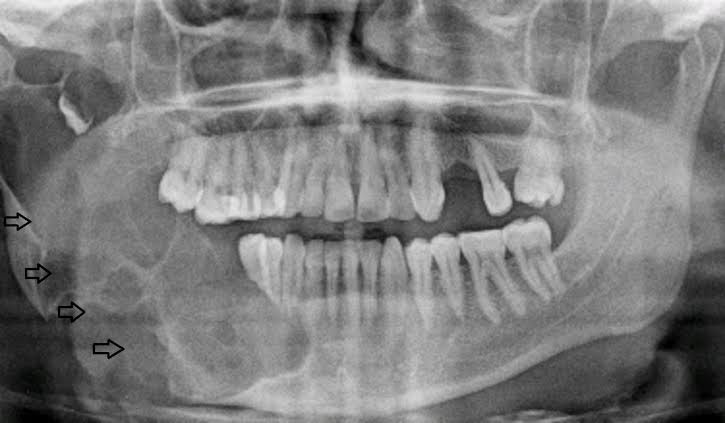

Ameloblastoma is a rare, noncancerous (benign) tumor that develops most often in the jaw near the molars. Ameloblastoma begins in the cells that form the protective enamel lining on your teeth. The most common type of ameloblastoma is aggressive, forming a large tumor and growing into the jawbone.